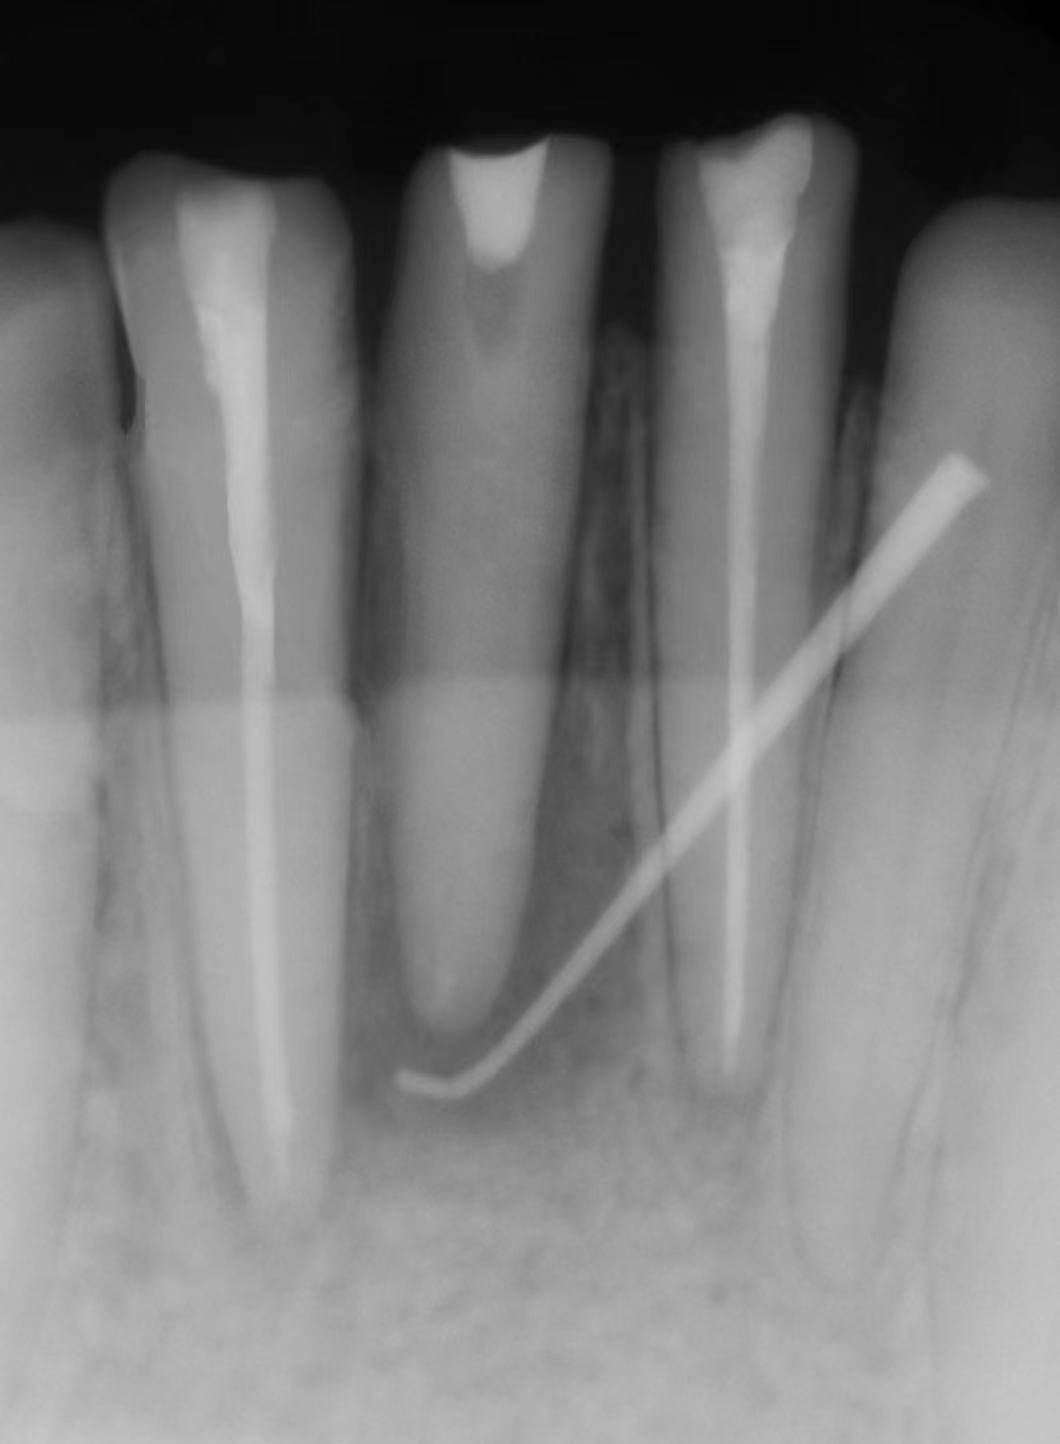

大多数情况下

窦道口都位于病灶牙相应的牙龈表面,

但是也偶尔会有

开口位于远离病灶牙的情况,

这就需要医生的火眼金睛来精准定位啦,

必要时可自窦道口插入诊断丝

拍摄X线示踪片以确定窦道的来源。

( 根管治疗前后对比图)